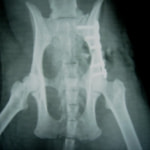

骨盤骨折 : 症例1 | 症例2 | 症例3 | 症例4

症例:交通事故による椎体脱臼

柴犬:9歳、避妊雌

交通事故直後、胸腰部に激しい疼痛、両後肢に完全麻痺を認め、シェフシェリントン徴候を呈していました。レントゲン検査において、第11-12胸椎間の脱臼が認められました。

脊髄の減圧、脊柱管の再構築・安定化を目的に、片側椎弓切除術およびMatrixMANDIBLE Plateによる椎体固定を実施しました。

隣接椎体を架橋するようにプレートを設置しました。

術後レントゲン写真